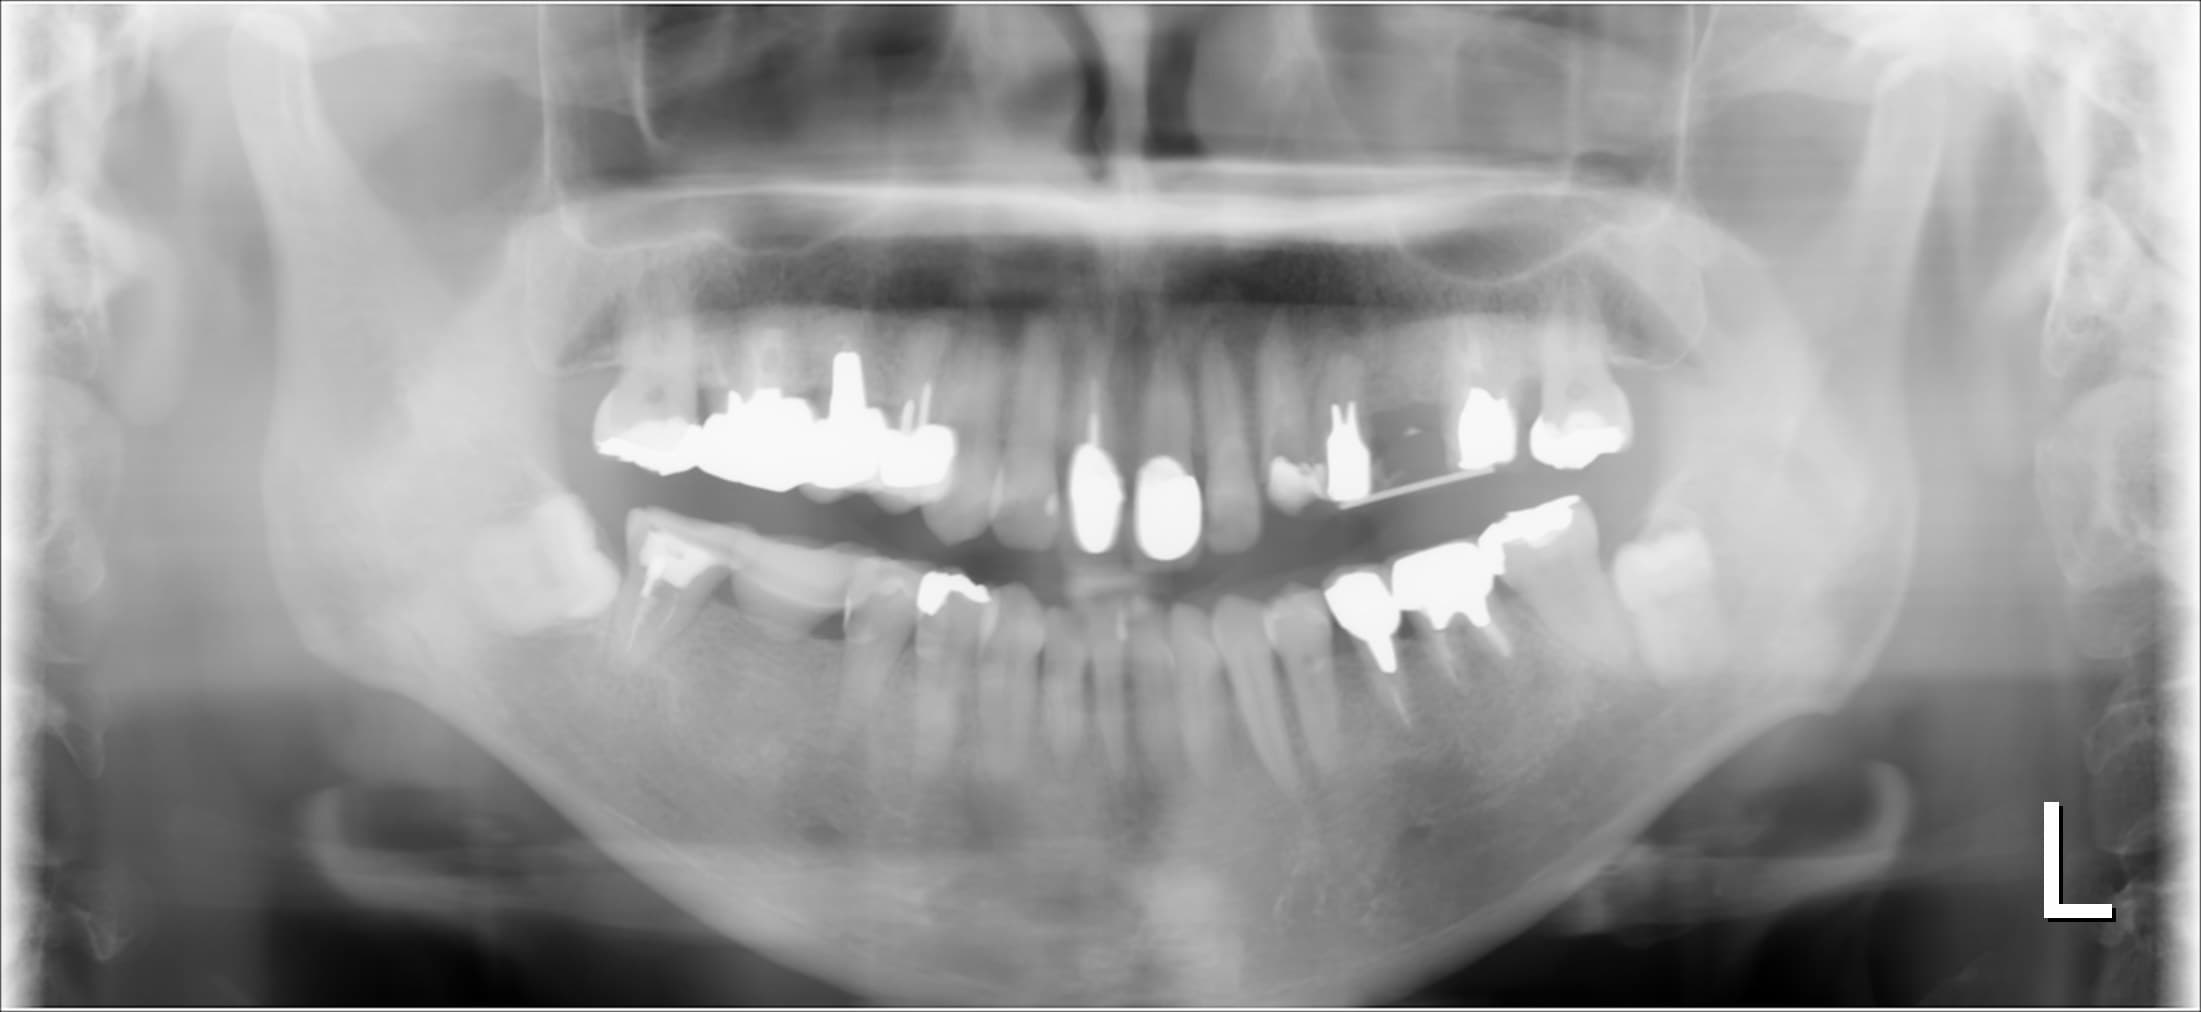

今回ご紹介する歯周専門治療のケースは、50代女性の方です。

他院にて、メインテナンス管理と根の治療を行っていましたが、改善されず、悩みに悩みぬいて当院へ相談にいらっしゃいました。

↓治療前

左上の根の治療が途中の所は、歯肉に軽く触るだけで簡単に歯肉から出血する状況でした。

また、歯と歯の間の歯肉も赤く腫れているのがわかります。